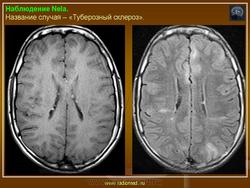

Факоматозы. Туберозный склероз, или синдром Бурневиля - Прингля 1. +

Туберозный склероз, или синдром Бурневиля - Прингля.

Туберозный склероз (болезнь Бурневилля-Прингла, синдром Бурневилля - Брессау) - глиоз белого вещества мозга, проявляющийся в раннем детстве эпилептическими припадками (в 85%), олигофренией в сочетании с нараста­ющей пирамидной и экстрапирамидной симптоматикой, кожной патологией. В возрасте 4-6 лет на лице в форме бабочки в области носа обычно появляют­ся множественные желто-розовые или коричнево-красные узелки диаметром чуть больше 1 мм - аденомы Прингла, которые обычно признаются аденомами сальных желез, однако есть мнение и о том, что они представляют собой про­исходящую из нервных элементов кожи гамартрому.

На поверхности мозга наблюдаются единичные или множественные глиома-тозные узлы, по цвету несколько светлее окружающего мозга и плотнее его на ошупь, возможна их кальцификация. Узлы могут быть и в белом веществе, под­корковых ганглиях, а также в стволе мозга и в мозжечке.

Встречаются и аномалии развития извилин мозга в виде микро- и пахигирии. Заболевание чаще носит спорадический характер. Бляшки достигают диаметра 5-20 мм. В коре больших полушарий и мозжечка иногда могут быть обнару­жены пластинчатые тельца, напоминающие амилоид. Происходит дегенерация клеток коры. При КТ-исследовании головы нередко можно выявить кальцифика-ты и глиальные узелки в паравентрикулярной области, субэпендимарно вдоль на­ружных стенок боковых желудочков, в зоне межжелудочкового отверстия Мон­ро, реже - в мозговой паренхиме. На М РТ головного мозга в 60% выявляются гипотеденсивные очаги в одной или обеих затылочных долях, которые расце­ниваются как участки неправильной миелинизации (Козлов А.В., 2002).